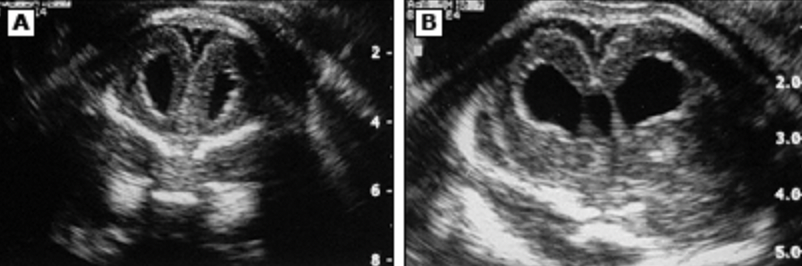

颅脑超声、CT平扫或MRI等检查可发现CMV中枢神经系统损害(图1-3)。在胎儿和小婴儿中,已知神经影像学的表现包括:脑室周围钙化灶、豆状核纹状体血管病变、脑室扩张、白质病变、移行异常(局灶多小脑回、巨脑回和无脑回)及脑室周围白质软化和囊性变。其他少见的影像表现包括脑室分隔或粘连、脑萎缩、胼胝体发育不全和小脑发育不全。头颅影像学异常与长期神经发育不良结局相关,特别是小头畸形、颅内钙化和移行异常。在年长儿和成人中,影像表现则与病毒感染轻重有关,MRI检查可表现为脑水肿,大脑皮层、灰白质交界区、丘脑或基底节异常信号影。